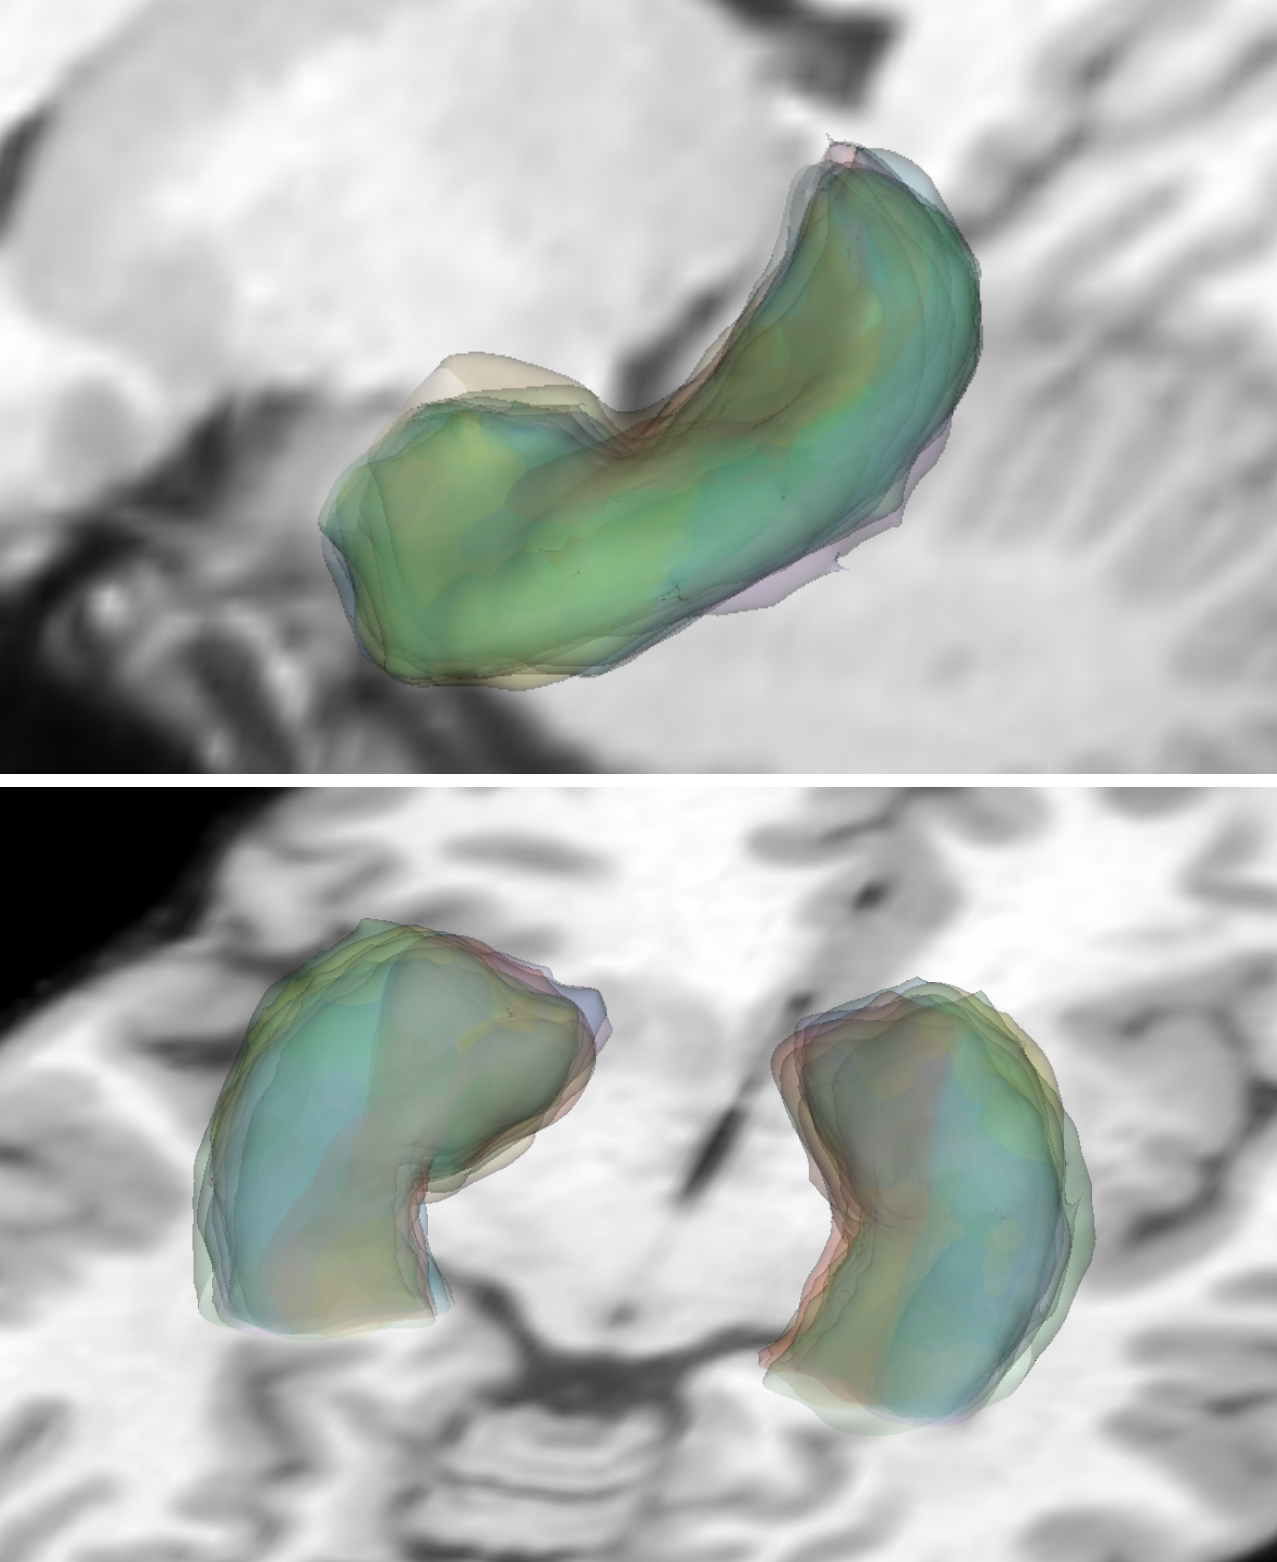

[Spaghetti plots of hippocampus on 2D slices (20 members)]

[3D spaghetti plots of hippocampus]

[3D contour plots of hippocampus]

[Spaghetti plots of ventricles on 2D slices (20 members)]

[3D spaghetti plots of ventricles]

[3D contour plots of ventricles]

5.2 IXI Dataset

Our method can be used to effectively process 3D binary masks using the binary specialization of GPU PID-mean. Examples are shown for the publicly available Information eXtraction from Images (IXI) dataset [antonelli2022medical]222https://brain-development.org/ixi-dataset/. Specifically, we use 400 T1-weighted MRI volumes of size .

For structure-specific analysis, we consider the segmentation labels of the hippocampus (Fig.˜9(a, b, c)) and the third and fourth ventricles (Fig.˜9(d, e, f)). Binary contours of a few members are visualized as spaghetti plots on 2D slices (Fig.˜9(a, d)) and as 3D isosurfaces (Fig.˜9(b, e)). These spaghetti plots reveal the fine structures of the contours but are already cluttered, especially for the 3D cases, which suffer from severe occlusions.

Clear visualizations are achieved with 3D contour boxplots generated from the PID-mean outputs. Contour boxplots of the hippocampus (Fig.˜9(c)) reveal the high agreement between the envelope of 50% (orange) members and 100% members (blue), and the median member (yellow) shows the representative shape and size of the ensemble. While for the ventricles, contour boxplots (Fig.˜9(f)) show that there is visible space between the envelope of the 50% members and that of the 100% members, the median member reveals the typical ventricles of the ensemble. Regions inside the interior surfaces are small, indicating that variations between members are rather large.

PID-mean helps gain insights into the trends of complex anatomical structures within the binary contour ensemble. The example demonstrates that PID-mean has the potential for analyzing specific medical problems in cohort studies using ensembles of medical images.